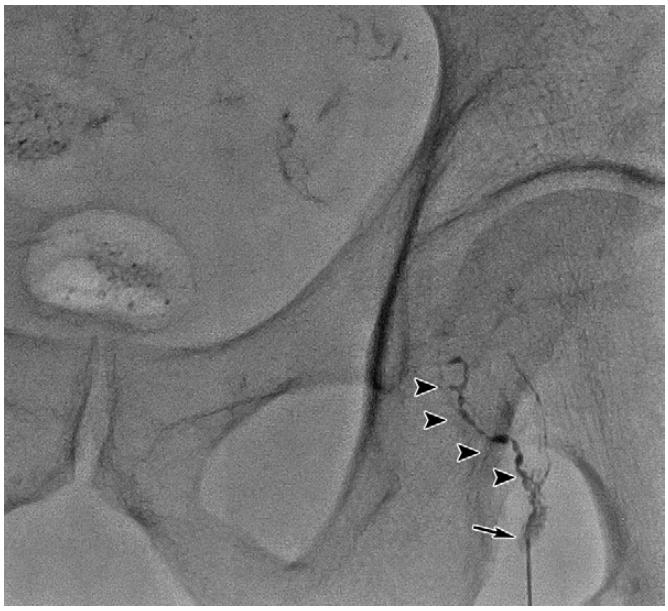

DSA下淋巴管造影

当实时显影出现与淋巴囊肿相连接的淋巴管时即可进行栓塞治疗。淋巴管栓塞治疗术后仍需密切观察淋巴囊肿引流量。

淋巴管造影+栓塞治疗